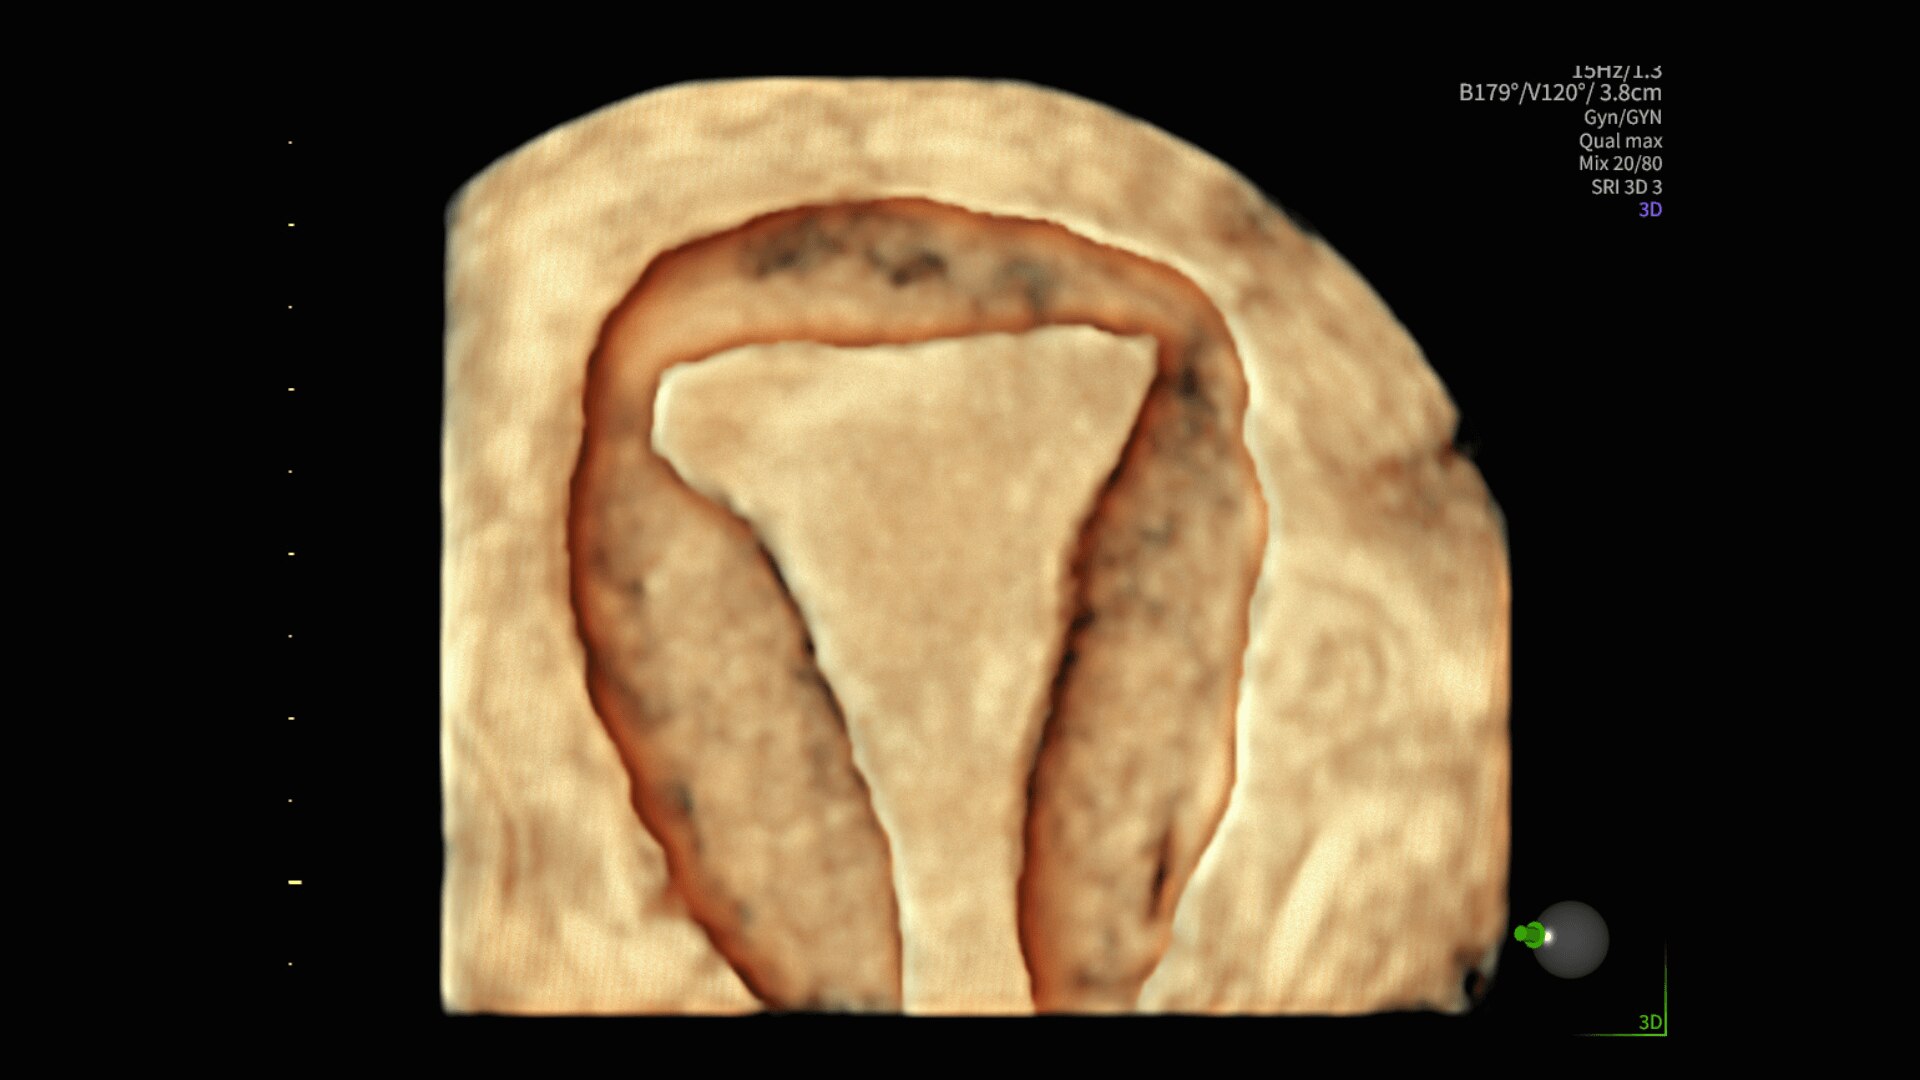

88%

Segment fibroids with 88% accuracy using Fibroid Mapping